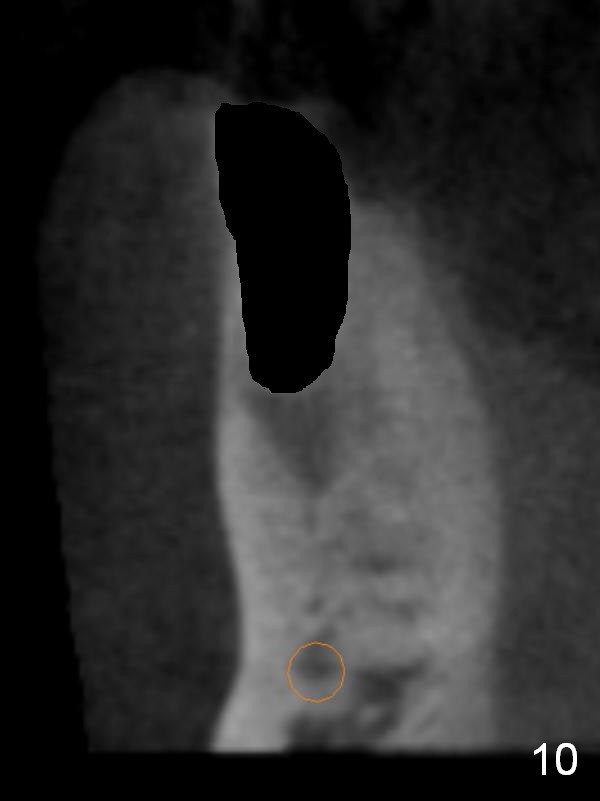

CT sagittal section shows that it is possible to place 4.5x20 mm implant (Fig.6). Axial (Fig.7) and coronal (Fig.9) sections show that the lingual (L) plate is much thicker than the buccal (B) one. To prevent the implant being buccally deviated, a Lindermann bur is used after extraction (black area in Fig.8,10) to remove ~ 1mm bone from the lingual plate (red area in Fig.8,11). A 2 mm pilot drill is placed as lingual as possible (green in Fig.8,11). If the implant (Fig.12) starts to deviate buccally while being placed, remove it from the osteotomy and remove more bone from the lingual plate. Place the implant again and monitor the trajectory tightly.